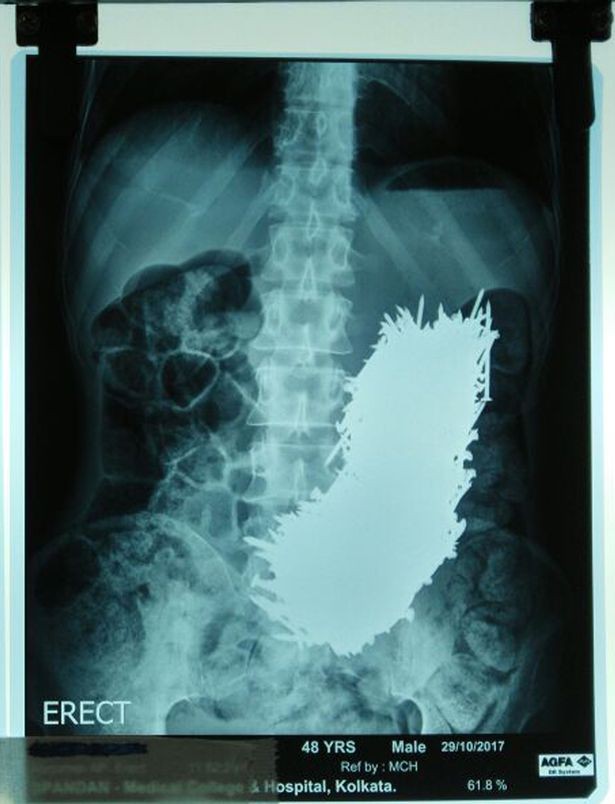

Ông Kumar được cấp cứu vào bệnh viện trong t́nh trạng đau bụng quằng quại. Sau khi nh́n kết quả siêu âm, cả bác sĩ lẫn nhân viên bệnh viện đều tá hỏa. Khoảng 600 chiếc đinh bằng thép nằm trong dạ dày.

Phim chụp siêu âm có phần... kinh dị của ông Kumar.

Tiến sĩ Siddhartha Biswas, người lănh đạo đội ngũ y tế tại Đại học Y khoa và Bệnh viện Calcutta - Ấn Độ, nói: "Tôi là một bác sĩ khách mời tại pḥng khám địa phương ở làng Dhali. Tháng trước, gia đ́nh ông đă đưa bản báo cáo siêu âm cho chúng tôi, và tôi đă bị s.o^.c nặng khi t́m thấy 600 chiếc đinh thép trong bụng ông".

"Chúng tôi quyết định phẫu thuật cho anh ta. Có nguy cơ cao là bụng ông ta sẽ bị chướng và dạ dày bị đâm thủng do các đinh thép, nhưng may mắn thay điều đó đă không xảy ra".

"Chúng tôi cắt một phần dạ dày của Kumar và dùng một nam châm để hút từng chiếc đinh thép, mỗi chiếc một lần, trong đó có hơn 600 chiếc đinh thép. Chúng tôi làm hết sức cẩn thận để chắc chắn rằng tất cả đinh mà ông ấy đă nuốt đều phải được lấy ra".